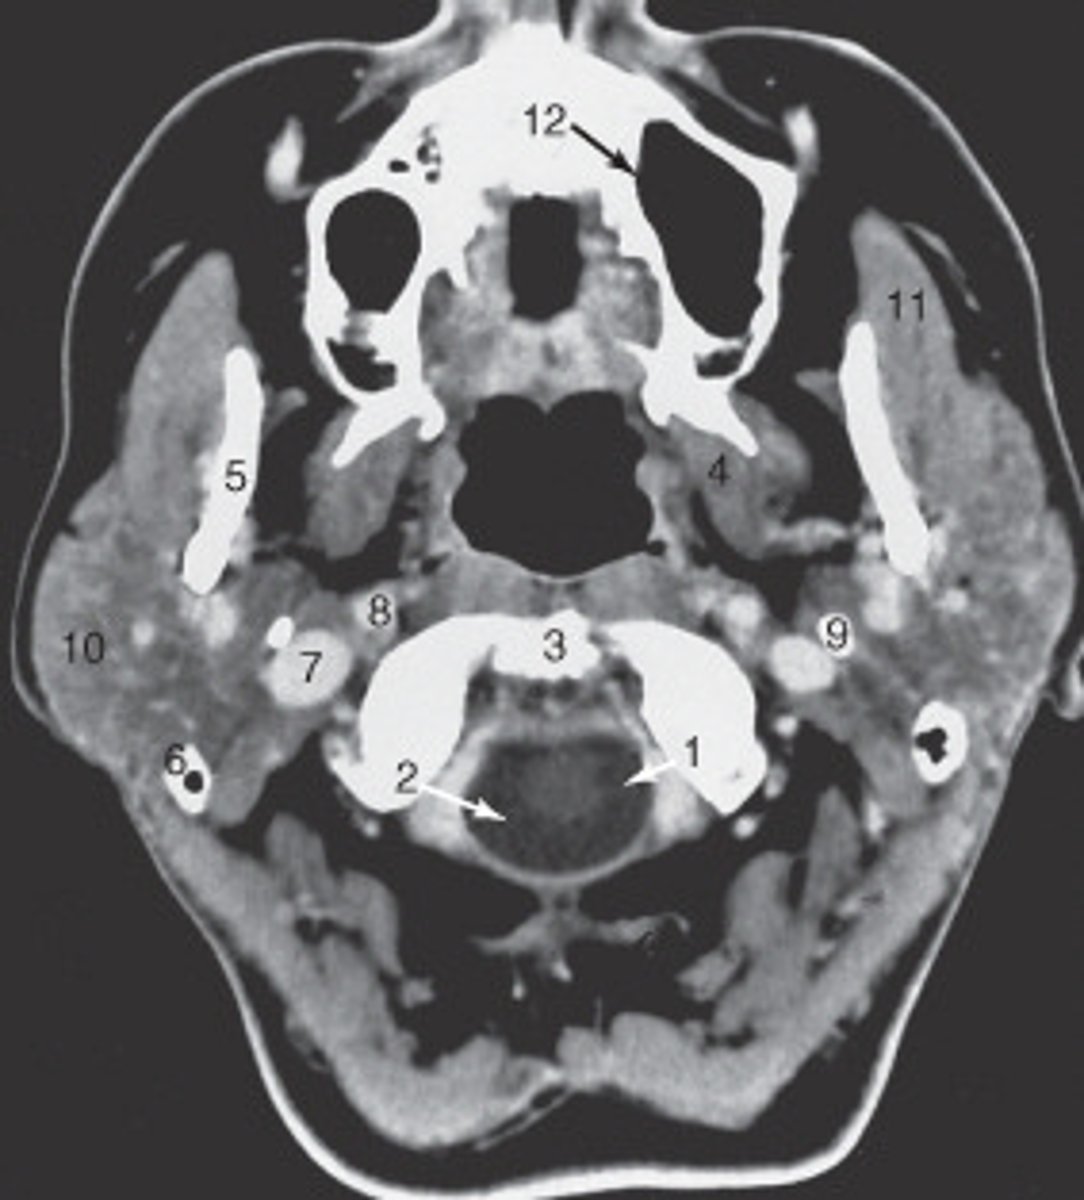

the mastoid air cells are labeled:

<p>the mastoid air cells are labeled:</p>

the structure labeled 6 is the:

<p>the structure labeled 6 is the:</p>

the structure labeled 5 is the:

<p>the structure labeled 5 is the:</p>

The internal jugular vein is labeled:

<p>The internal jugular vein is labeled:</p>

the parotid gland is labeled:

<p>the parotid gland is labeled:</p>

the structure labeled as 8 is the:

<p>the structure labeled as 8 is the:</p>

The structure labeled as 1 is the:

<p>The structure labeled as 1 is the:</p>

The thyroid cartilage is labeled:

<p>The thyroid cartilage is labeled:</p>

The common carotid artery is labeled:

<p>The common carotid artery is labeled:</p>

The structure labeled as 5 is the:

<p>The structure labeled as 5 is the:</p>

the intervertebral disk is labeled:

<p>the intervertebral disk is labeled:</p>

The structure labeled as 4 is the:

<p>The structure labeled as 4 is the:</p>